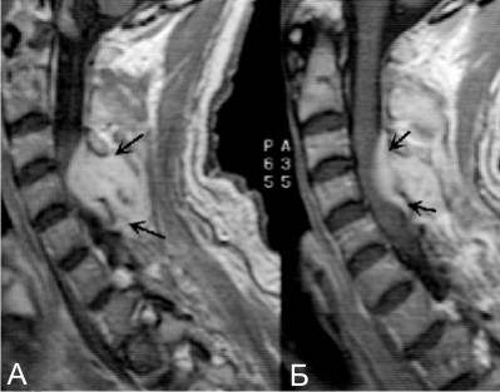

Диагностические процедуры для выявления данной патологии включают:

- анализы крови, мочи и гнойного материала;

- компьютерную томографию;

- магнитно-резонансную томографию;

- миелографию.

Полное инструментальное обследование позволяет определить место воспалительного процесса, пути проникновения инфекции в эпидуральное пространство, плотность костных тканей и другие важные параметры, что способствует правильной интерпретации результатов.

Как диагностируется и лечится эпидуральный абсцесс позвоночника?

Диагностика эпидурального абсцесса обычно включает магнитно-резонансную томографию (МРТ) или компьютерную томографию (КТ) для визуализации области. Лечение может включать антибиотикотерапию и, в некоторых случаях, хирургическое вмешательство для дренирования абсцесса и удаления источника инфекции.